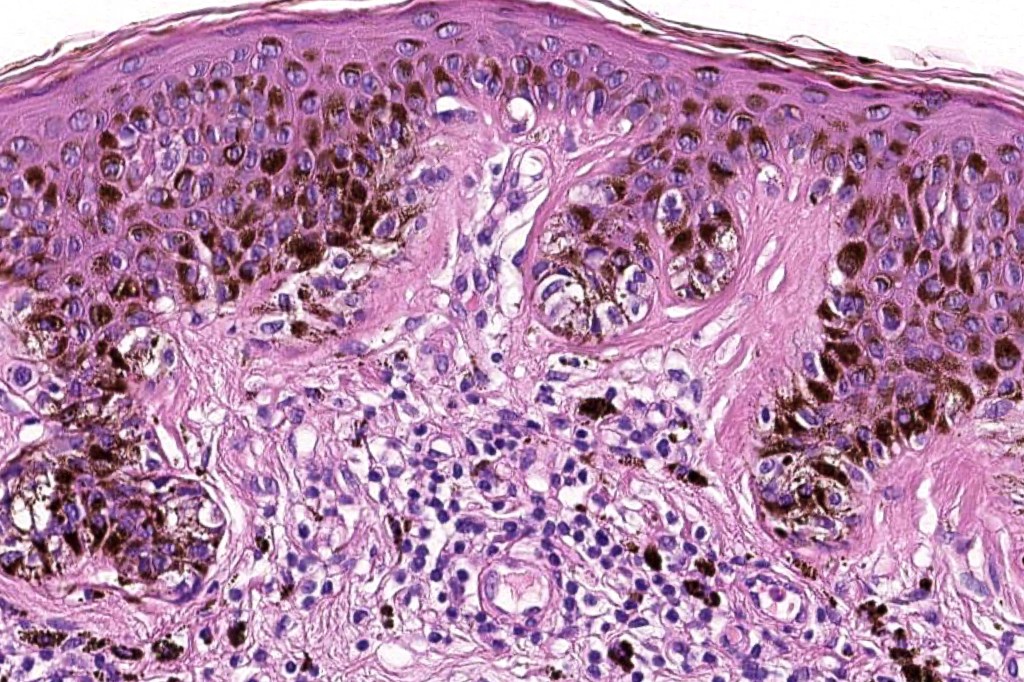

Histological features

•Architectural disorder- lentiginous and nested, nests abnormally located (at the sides of the rete ridges & overlying the dermal papillae in addition to the tips of the rete ridges rather than solely occupying the tips of the rete ridges as is seen in banal nevi), horizontal orientation & bridging between junctional nests (this should not be confused with bridging between adjacent rete ridge squamous epithelium)

•Abnormal fine pigmentation (dusty)

•Host response- eosinophilic & lamellar fibroplasia, increased vascularity, lymphocytic infiltration & pigment incontinence

Dysplastic nevus in the majority of cases is instantly recognizable, often at low power. The most important differential diagnosis is obviously melanoma. In junctional lesions, widespread/uniform high grade atypia, frequent mitoses and Pagetoid spread are indicative of in situ melanoma. In compound lesions, dermal nests larger than junctional ones, expansile dermal nests, severe atypia and mitotic activity indicate the presence of melanoma